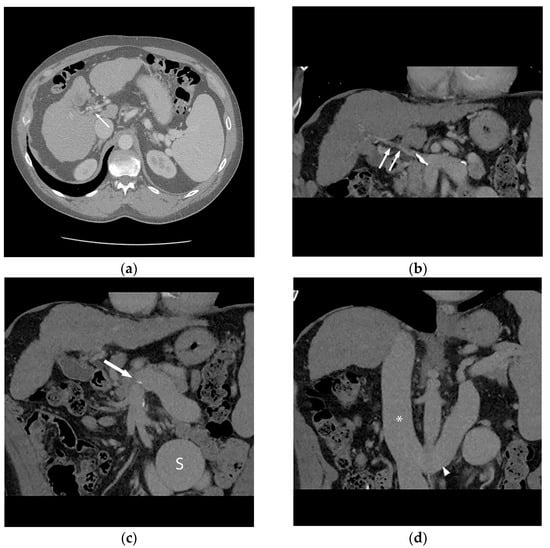

PVR-TIPS techniques: The ability to successfully perform a PVR-TIPS requires mastery of several core building-block techniques that are generally employed in step-wise fashion (Figure 2). First, the steps of a standard TIPS placement procedure should be performed, including obtaining right internal jugular vein access, placement of a 10 Fr sheath, obtaining a baseline right atrial pressure measurement, and catheterization of the right hepatic vein [42,43,44]. Once in position, the cannula device from a TIPS kit is then placed within the sheath, and in cases of partially or minimally occlusive thrombosis, access into the portal vein is obtained utilizing standard techniques. In complete or chronic occlusion (with or without cavernous transformation), transhepatic or transplenic techniques are utilized to obtain access into the thrombosed portal system.

Figure 2.

In order to facilitate listing for liver transplantation, the patient (Figure 1) was referred for portal vein recanalization and transjugular intrahepatic portosystemic shunt (TIPS) placement. (a) This required both hepatic vein (HV) and splenic vein (SV) access, and a “gun-sight” technique (arrow) was used to reconstruct the portal vein. (b) With the TIPS deployed (arrow), the large shunt (S) was next addressed. (c) An inferior vena cava filter (arrow) was used in an off-label manner to form a scaffold for coil embolization of the large portosystemic shunt. Final angiography (d) demonstrates a patent TIPS (black arrow) and occluded portosystemic shunt (white arrow).

Initial series described transhepatic access to gain access into the thrombosed portal system; however, more recent series described a higher technical success rate for the procedure with the use of transplenic access into the portal system [43], which has been the experience at our center. In cases where transplenic access is unfavorable or unable to be employed, transmesenteric access has also been utilized as a possible method for portal vein recanalization [46]. In the case of transplenic access, a 21 G needle is advanced under ultrasound guidance into an intraparenchymal splenic vein branch and a 0.018 inch nitinol wire is advanced through the needle into the splenic vein. At this point, an Accustick sheath (Boston Scientific Corporation, Marlborough, MA, USA) is placed into the splenic vein and a long digital subtraction image of the portal venous system is obtained and portal pressures are obtained. Oftentimes, a faint diminutive caliber thrombosed portal vein can be identified coursing superiorly towards the liver hilum, and at this point utilizing an angled catheter and glide wire the portal vein is recanalized and a small amount of contrast is injected to confirm intrahepatic portal vasculature. Even in cases with extensive chronic thrombosis with cavernous transformation, a long DSA run will often opacify the obliterated portal vein or identify the coronary vein, which can be used as a landmark to identify the chronically thrombosed segment. Once access is confirmed, the main portal vein is dilated with an 8 mm high-pressure balloon to restore patency and facilitate TIPS access and placement. After balloon dilation, TIPS is performed via the standard technique via the right internal jugular access, and in the event of difficult access into the portal system, a snare is placed via the transplenic access in order to help target the access site and obtain through and through access. After obtaining portal access and measuring the tract length, stent deployment is carried out in a fashion so as to maximize the amount of unstented portal vein in order to facilitate end-to-end anastomosis during surgery (Figure 3). Additional considerations during stent placement include ensuring that the superior portion of the stent is not extended into the inferior vena cava or right atrium or that the inferior portion of the stent does not extend into the retropancreatic region. Additionally, it is worth noting that stent placement is highly center- and surgeon-dependent so these discussions should take place prior to the procedure. After stent deployment, the entirety of the stent and parenchymal tract is dilated with a 10 mm high pressure balloon and in the event of recalcitrant stenosis or thrombosis, a 12 mm high pressure balloon. Post-TIPS DSA images are obtained and in the event of large collateral vessels influencing portal vein and TIPS flow, these are embolized at the time of the procedure to maximize portal vein flow. At the conclusion of the procedure, post-TIPS creation main portal and right atrial pressures are obtained. The splenic access site may be closed utilizing gelfoam pledgets, although prior operators have reported the use of coils with high technical success [44].